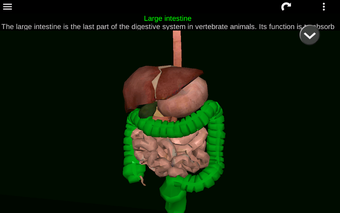

Diese Anwendung zeigt ein dreidimensionales Modell der menschlichen Körperorgane und eine Beschreibung aller von ihnen.

Sie können jedes Organ wie Herz, Gehirn, Lunge, Fortpflanzungssystem, Leber, Darm, Eierstock, Hoden, Magen, Niere usw. anfassen.

Sie ist für alle Menschen nützlich, auch für Studenten, da jedes Anatomieorgan in einer anderen Farbe dargestellt ist.

Sie können die App verwenden, um herauszufinden, welches die verschiedenen Körperorgane sind und welche Funktionen sie haben.